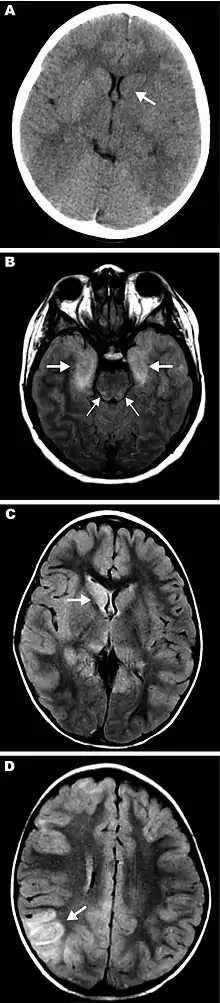

Magnetic resonance images (MRIs) and computed tomography (CT) neuroradiographs showing lesions in brains of three children with eastern equine encephalitis: A) Results of noncontrast CT scan of the brain of patient 12 on hospital day 2; the neuroradiograph shows subtle hypoattenuation of the left caudate head (arrow) and diencephalic region. B) Axial fluid attenuated inversion recovery image from brain MRI scan of patient 14 on hospital day 2; the image shows abnormal T2 hyperintense regions of the bimesial temporal regions (thick arrows) with accompanying abnormal T2 hyperintense regions of the dorsal pontomesencephalic regions (thin arrows). C, D) FLAIR images from brain MRI scan of patient 15 on hospital day 3. C) Abnormal T2 hyperintense caudate and thalamic nuclei, most prominent on the right (arrow). D) Abnormal T2 hyperintense regions are most prominent in the right parietotemporal gray matter (arrow) and subcortical white matter but are also seen scattered throughout.